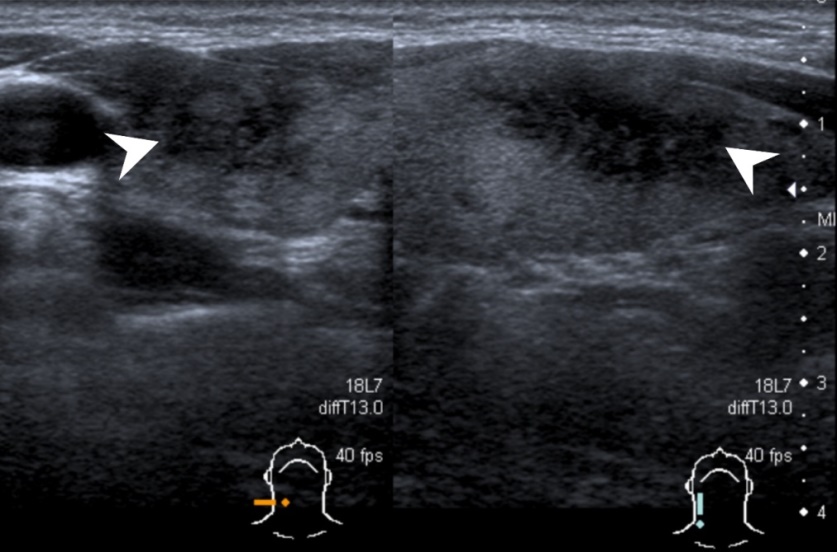

▲甲狀腺超音波可以看到發炎部位呈現低迴音。